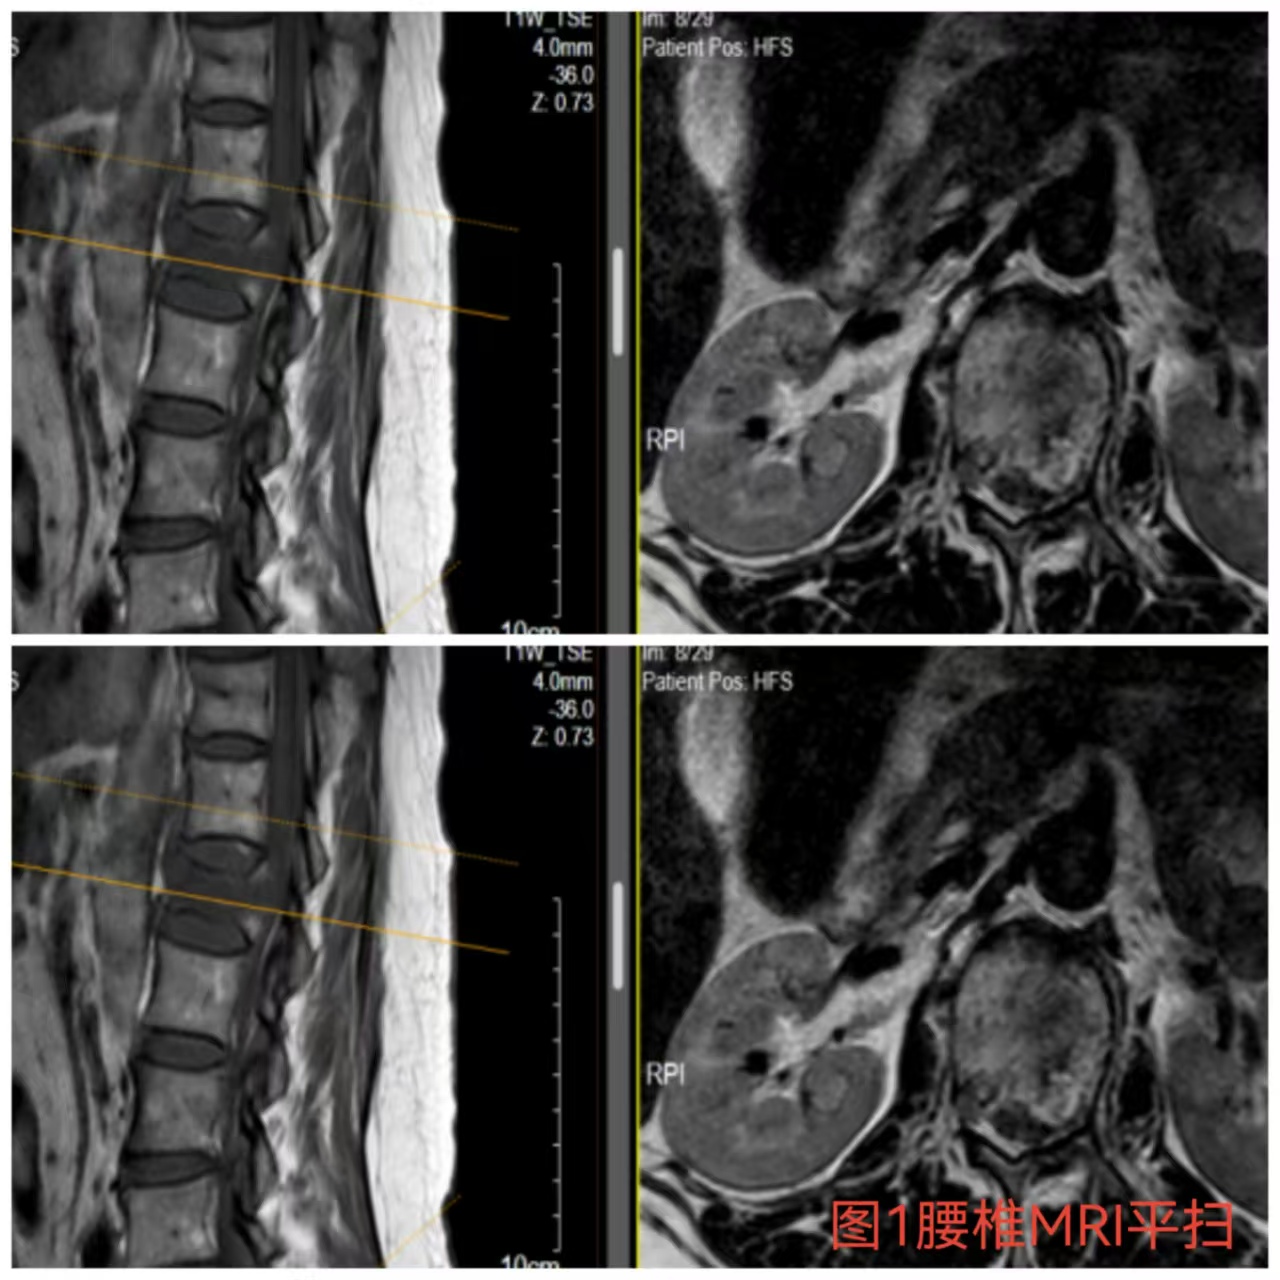

入院時(shí)患者躺在床上不能動(dòng)彈,眼神中透漏著(zhù)深深的無(wú)助,對于她來(lái)說(shuō)這種傷情無(wú)疑是沉重的,尤其是腹股溝以下感覺(jué)消失、雙下肢肌力0級,這意味著(zhù)其下肢無(wú)法活動(dòng)及站立,仿佛被命運按下了暫停鍵;與病人及家屬充分溝通病情后,第一時(shí)間給予對癥治療,監測患者生命體征,行腰椎核磁檢查(圖1)提示:腰1椎體爆裂性骨折,椎體后緣塌陷致骨性椎管狹窄,壓迫脊髓神經(jīng),結合患者病情及輔助檢查可診斷為:“L1椎體爆裂性骨折伴雙下肢截癱”。